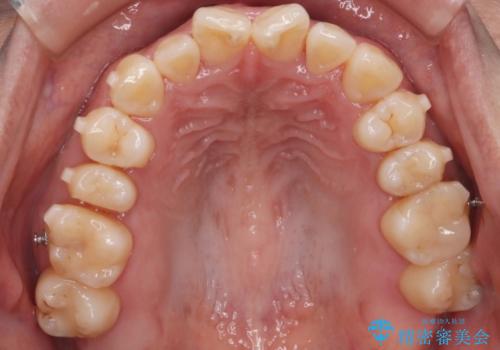

- 上の前歯の捻れを主訴に来院されました。

前歯の捻れとがたつきを改善するために、IPR(歯と歯の間を削る処置)と歯列拡大をすることで歯並びを整えていく治療計画を立てました。